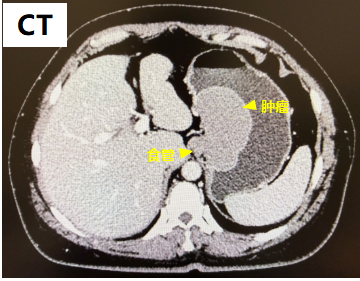

成人急诊科给予CT检查,提示胃小弯处有占位性病变,大小约8cm*4cm,接近成年人手掌大小,高女士被迅速收入普外科。

高女士入院后,普外科给予镇痛营养支持对症治疗,完善胸腹强化CT及胃肠镜检查。考虑胃间质瘤?平滑肌瘤?随后,所有检查资料被提交给了MDT团队。专家们拿到的不是零散的几张片子,而是一条完整的时间线和一个立体的病情画像。